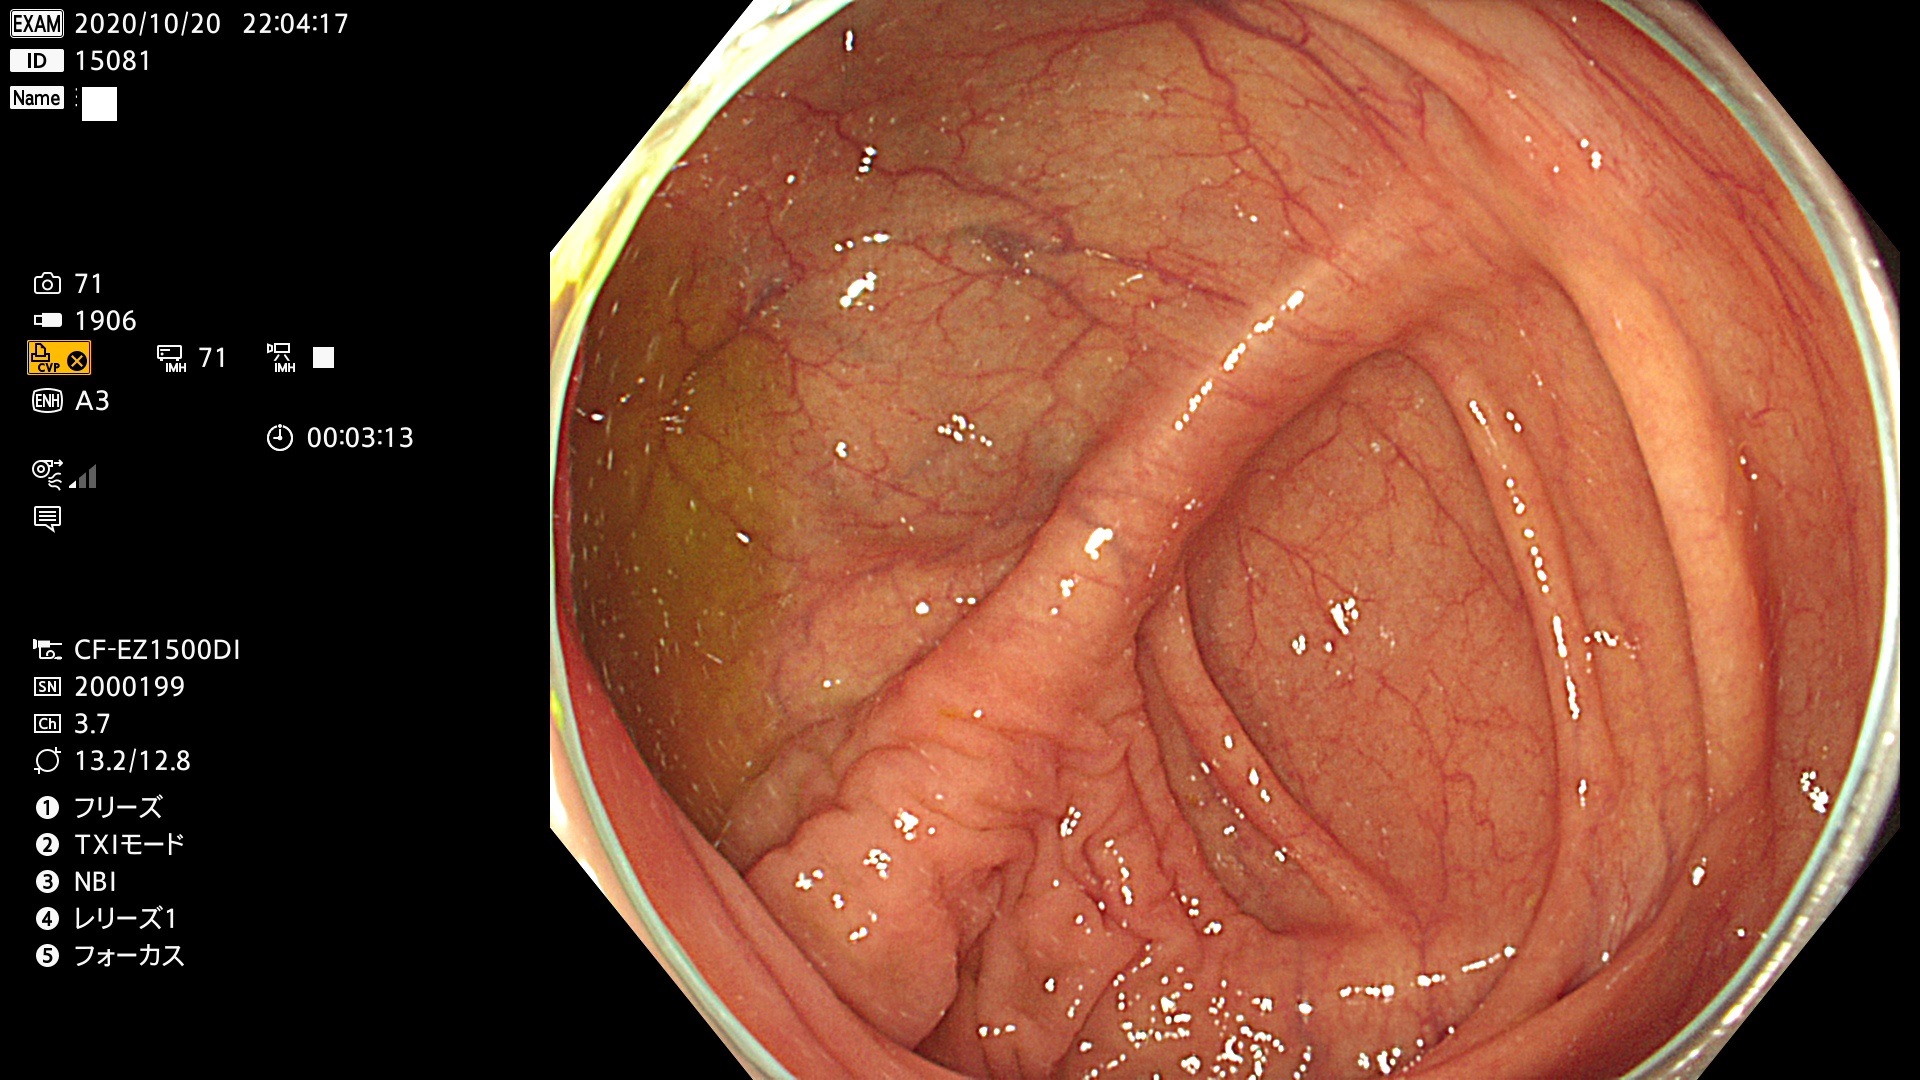

新型・大腸カメラ(1500型)の画像

私は、オリンパスの最初の電子スコープ(100型)から代々、使用していますが今回のモデルチェンジが(開発期間が長いからですが)最も画質の向上が著明と感じました。正確に4K解像度(3840X2160)ではないのですが従来の機種(290型)のハイビジョン画質(約1000X1000)を遥かに凌ぐ画質であることは確かです。残念ながら、この画質をWEBやUSB保存画像で確認することはできません。内視鏡の画像レコーダーが2K(1280X720)までしか対応していないため「2Kにダウンコンバート」して保存されるからです。検査室には2台の4Kモニターが設置されていますので検査中に「4K内視鏡」を御確認下さい。